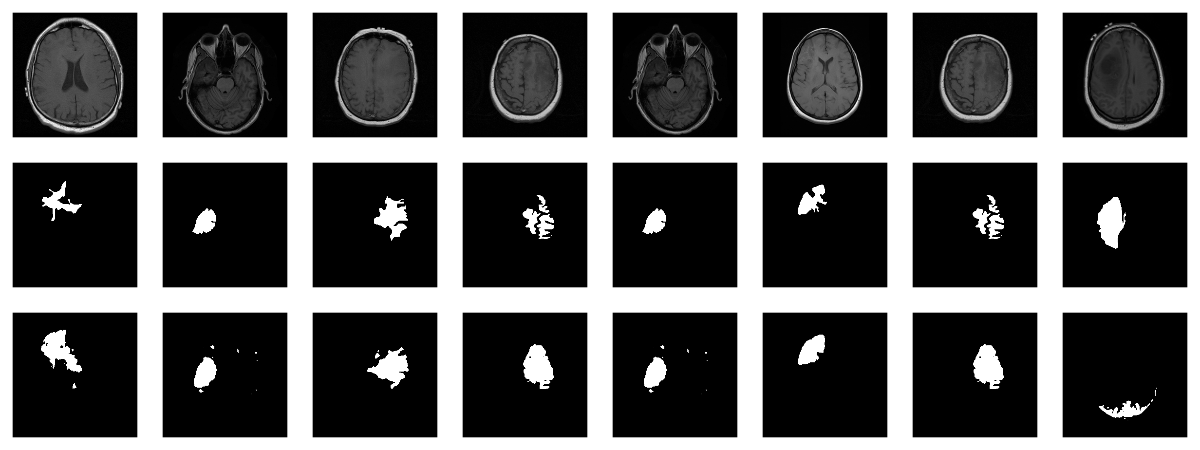

Here are three examples where the masks do indicate abnormalities:

Let’s see if we can build a U-Net that generates such masks for us.